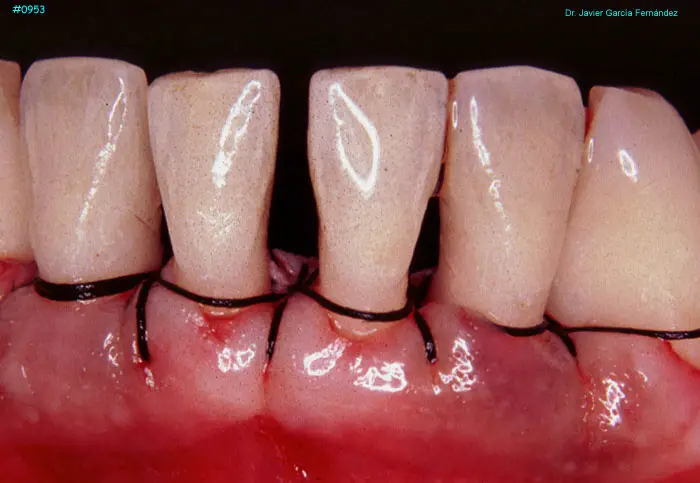

Atlas of Surgical Techniques in Periodontics. Chapter III. Atlas de Técnicas Quirúrgicas en Periodoncia

image360